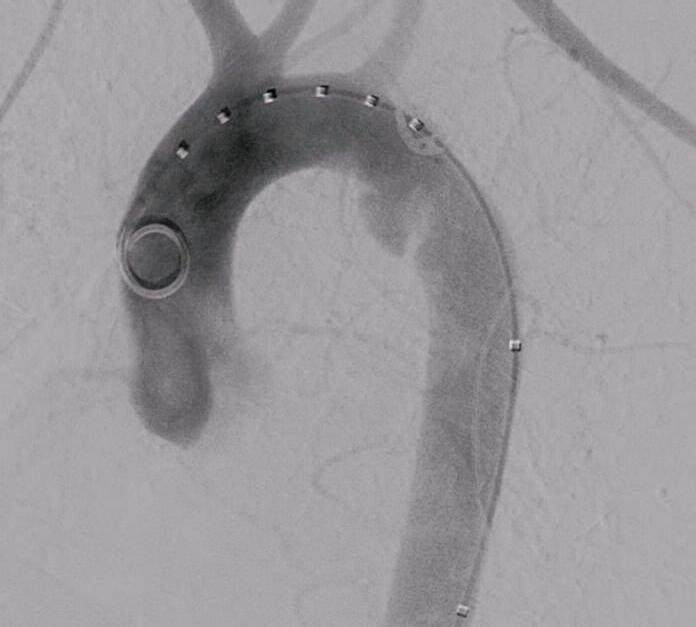

159 R i p a ra z i o n e t o t a l m e n t e e n d ova s c o l a r e d i u n a r o t t u ra dell’istmo aortico: caso clinico in un politrauma Totally endovascular repair of a traumatic aortic isthmic rupture:

a case report of a polytrauma patient

La rottura aortica rappresenta un'emergenza potenzialmente letale che può complicare un politrauma La stabilizzazione della lesione per via endovascolare costituisce un approccio terapeutico fattibile e rapido che consente di dedicarsi in un secondo momento alle altre lesioni ODDI F M , CARNEVALE R , FRESILLI M , IPPOLITI A